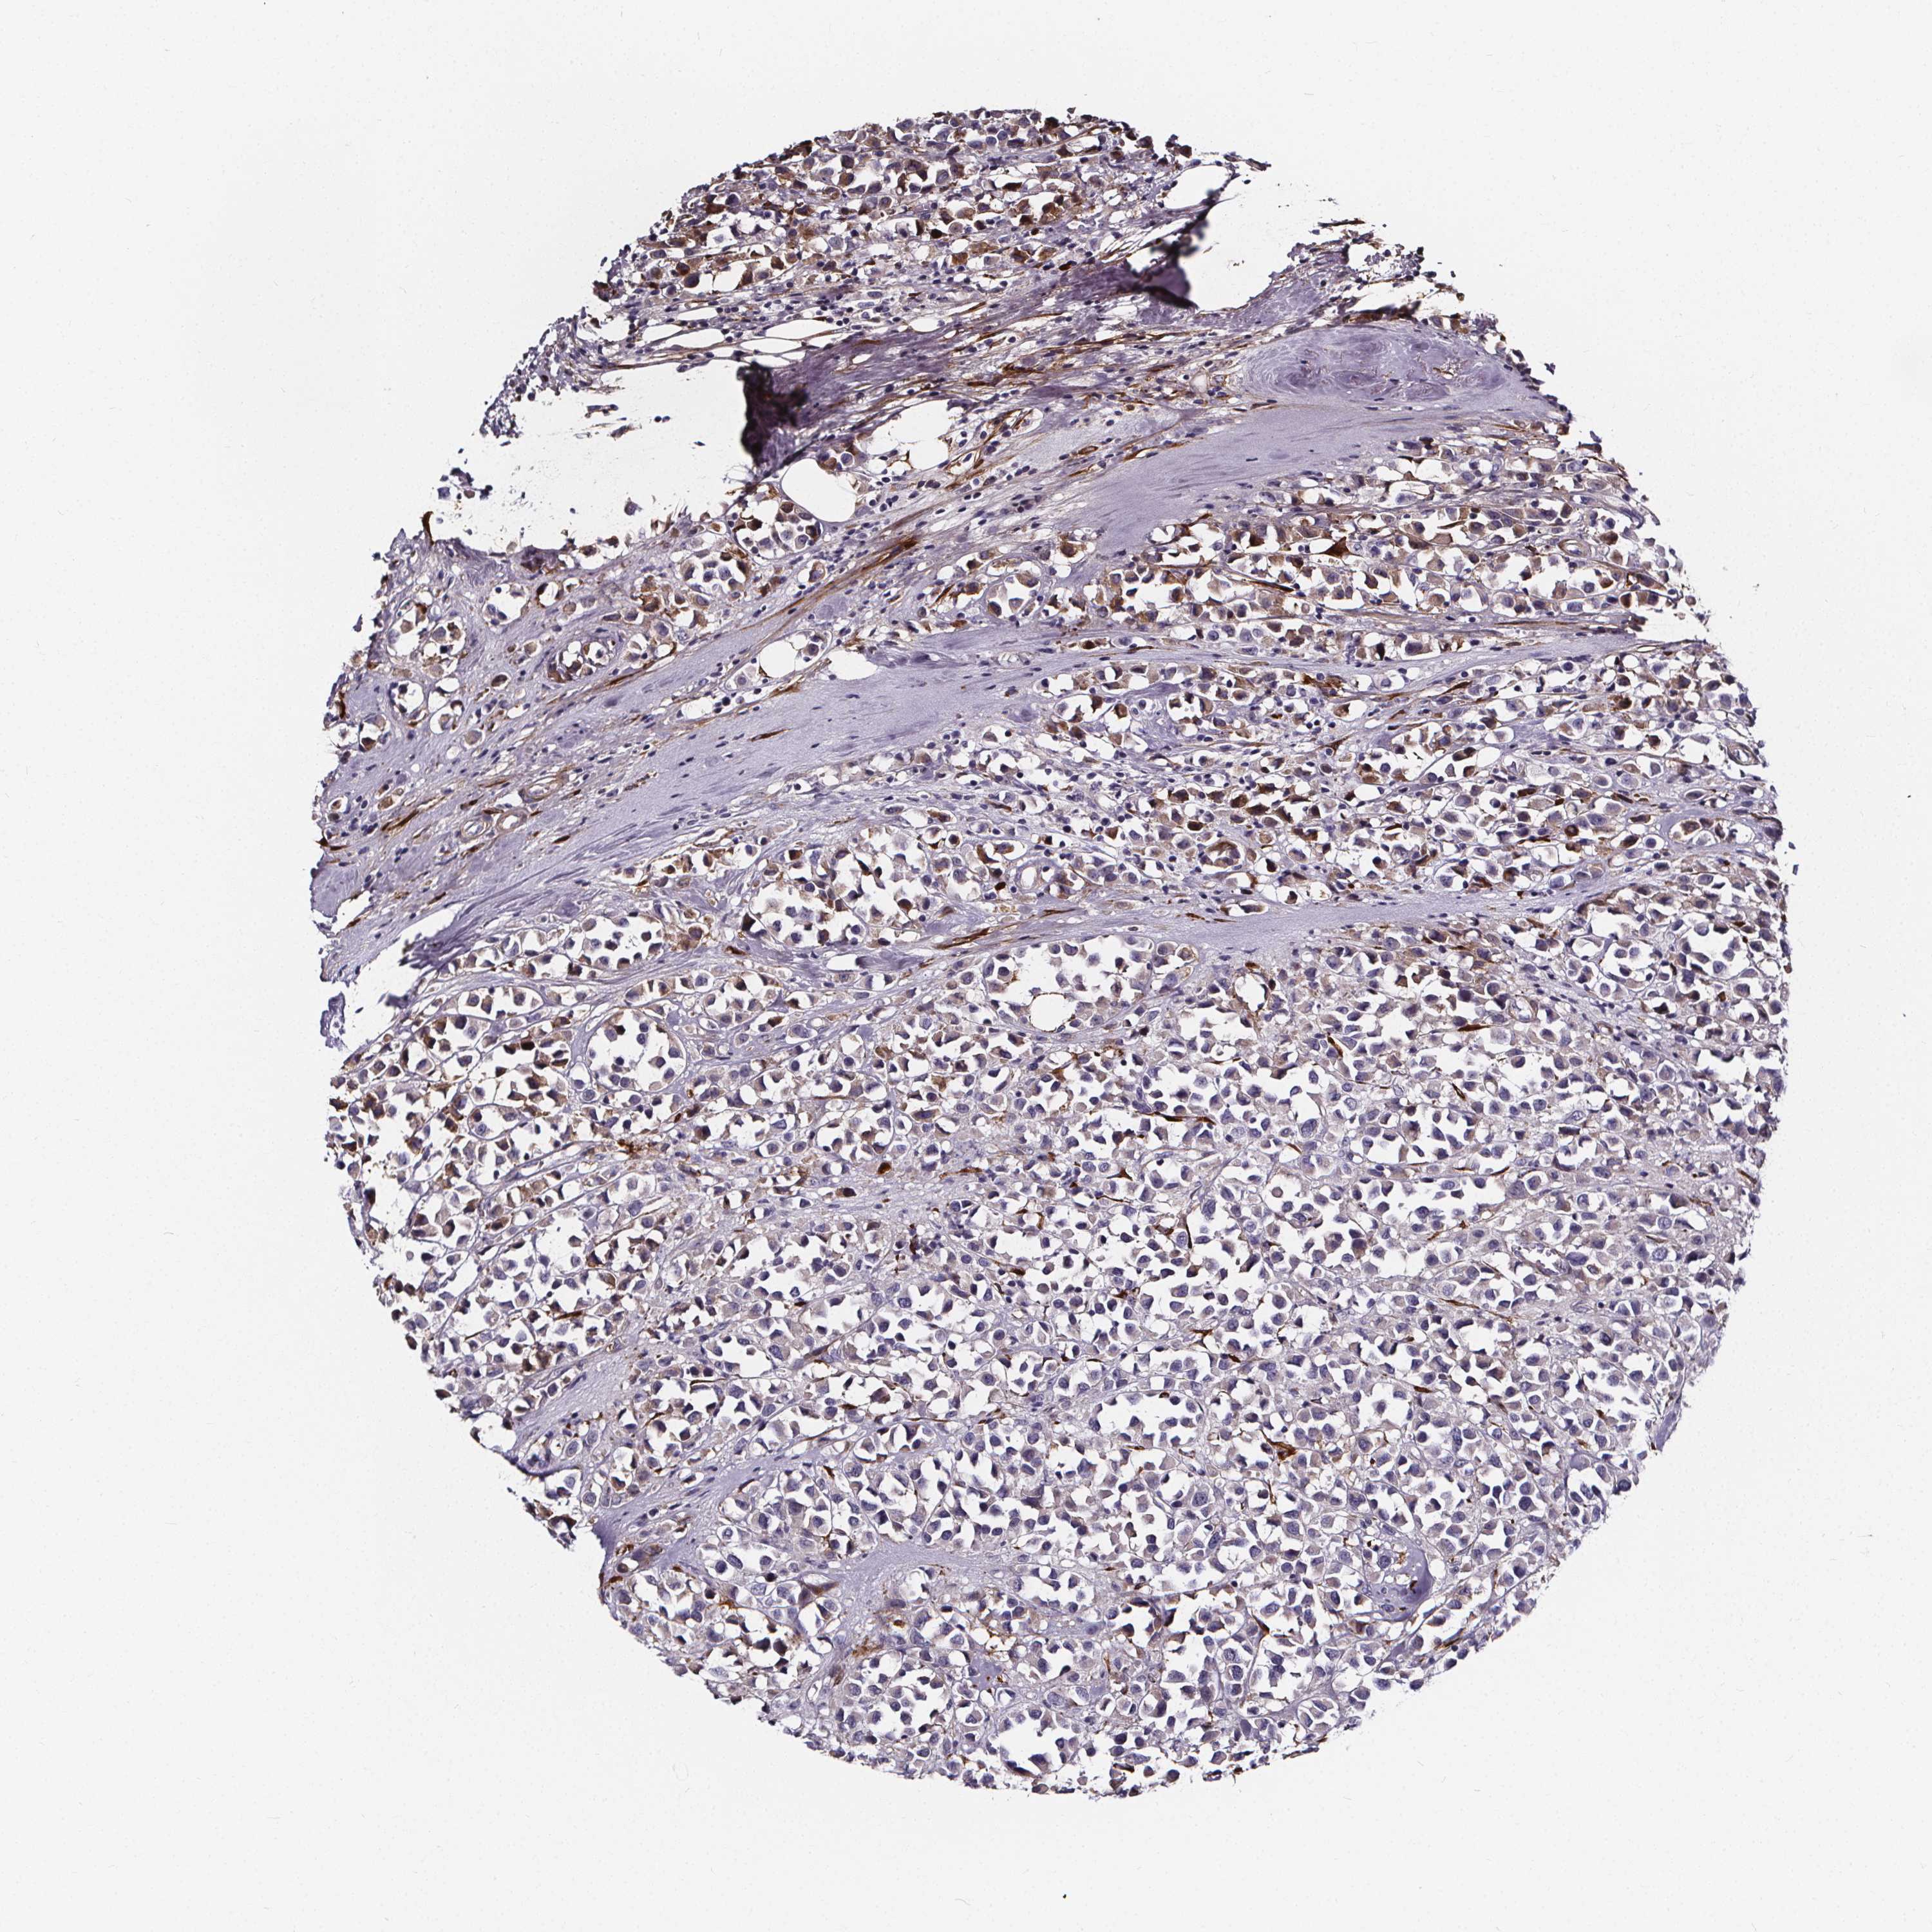

BRCA TCGA BRCA VALIDATION PROTEIN EXPRESSION